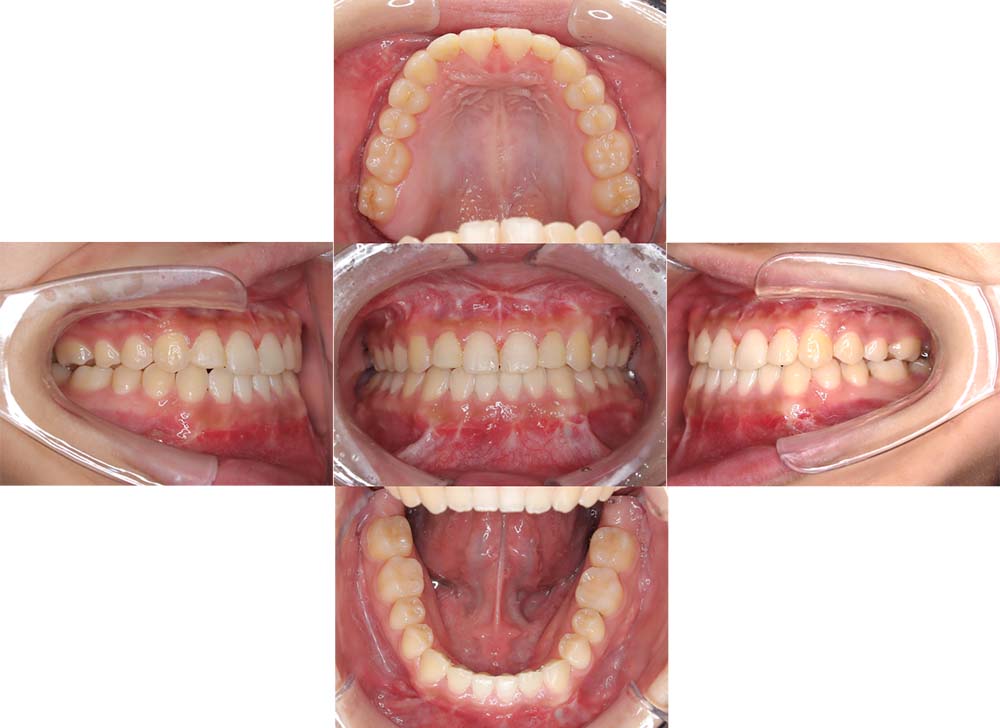

症例26

| 主訴 | 歯並びがガタガタしている。 |

| 診断名あるいは主な症状 | 叢生、上下顎前突、側方偏位 |

| 年齢/性別 | 25歳・女性 |

| 矯正ステージ | 大人の矯正治療 |

| 治療方法 |

ワイヤー矯正 アンカースクリュー |

| 抜歯部位/抜歯有無 | 上下顎両側第一小臼歯 |

|---|---|

| 治療内容 | 上下顎の抜歯によるスペースを使用し、ガタガタの改善と上下顎前歯を後退させた。 |

| 費用 |

90万円程度(2025.10時点の料金となります。) ※矯正基本料金、アンカースクリュー、審美ブラケットを含む |

| 治療期間 | 2年11ヶ月 |

| 主なリスク・副作用 | 痛み、歯根吸収、歯肉退縮、虫歯、後戻り |